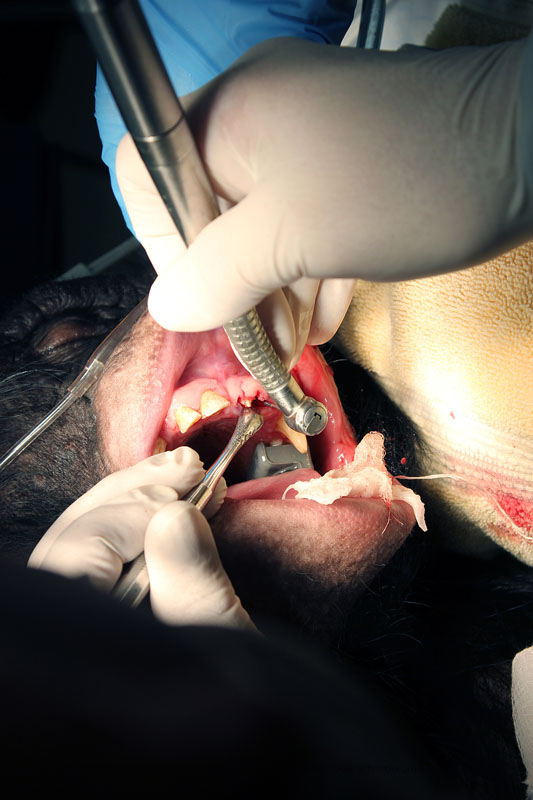

February, 2015Milwaukee County Zoo.Photos by Mark Scheuber, Zoo Keeper/Photographer

Maxillary left central incisor and lateral incisor residual roots. Region was inflamed, edematous prior to two weeks of antibiotic therapy.

Conventional dental film in position. Digital Phos Phor plates were also exposed.

Dr. Hausmann and Dr. Scheels positioning Nomad radiography unit.

Digital image reveals periapical lesion on central incisor residual root.

Incision on crest of ridge.

556 surgical bur used to remove approximately 2mm. of alveolar bone surrounding each root ("ditching".)

Luxator technique utilized to remove residual roots.